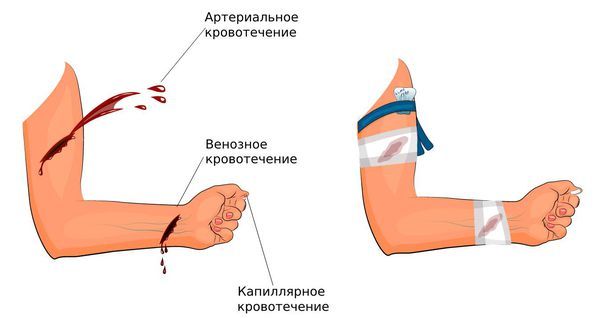

По типу пострадавшего сосуда кровотечения делятся на четыре вида:

- Артериальные. Такие кровотечения пульсирующие и сопровождаются обильным выделением алой крови [8]. Их объём определяется калибром сосуда и характером повреждения [1]. Этот вид относится к жизнеугрожающим.

- Венозные. Как правило, они менее интенсивные и протекают медленнее, при них выделяется тёмно-красная кровь. В случае травмы вены формируется гематома, которая сдавливает её, из-за чего кровотечение становится слабее.

- Капиллярные. Обычно возникают при незначительных травмах (порезах, уколах или ссадинах) мелких кровеносных сосудов. Такие кровотечения протекают очень медленно. В результате человек теряет немного крови, обычно в виде небольших капель, что редко приводит к серьёзным осложнениям. При травме кровоточит вся повреждённая поверхность.

Типы кровотечения и их остановка